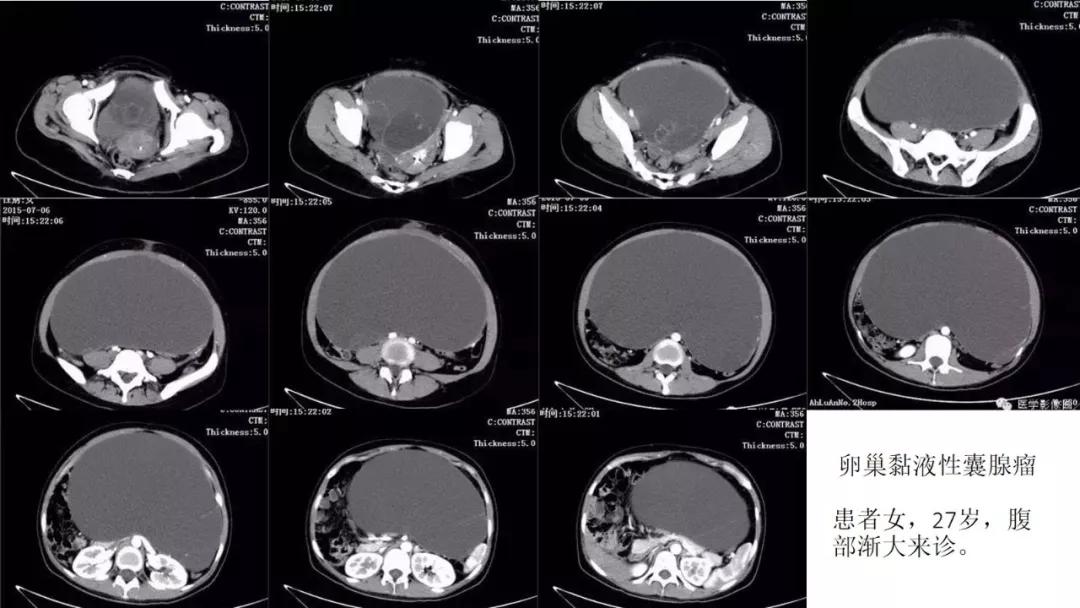

- 卵巢的黏液性肿瘤破裂,上皮和黏液会种植在腹膜引起胶冻样的腹膜假黏液瘤,这一点跟阑尾的黏液性肿瘤类似,都是腹膜假黏液瘤的病因。